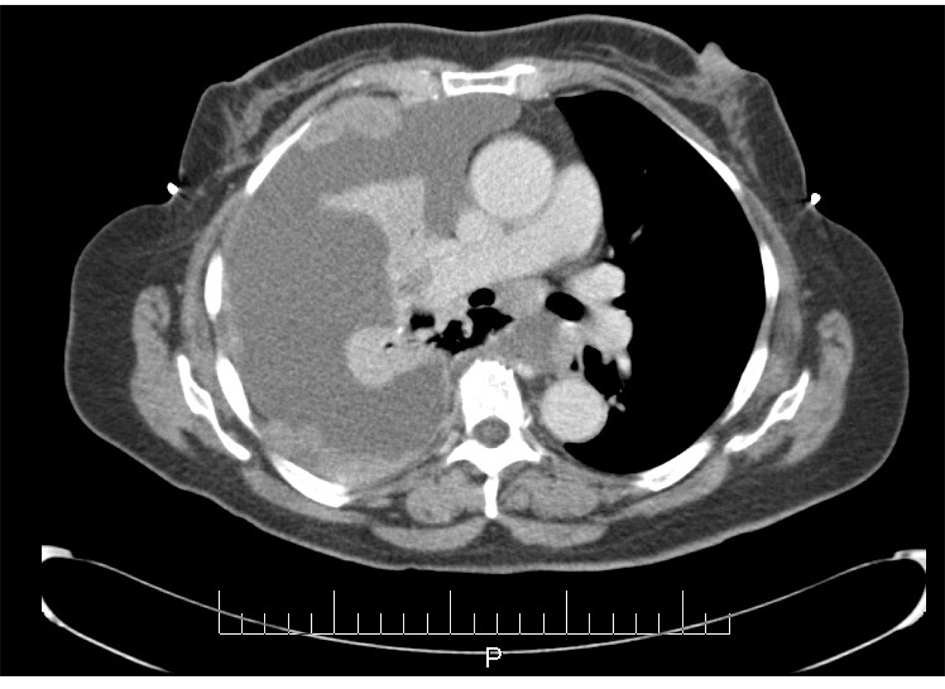

In June 1997, a 65-year-old G9P009 African-American woman was treated for FIGO stage IIA UPSC with total abdominal hysterectomy, bilateral salpingo-oophorectomy, and pelvic lymphadenectomy with 32P catheter placement, followed by adjuvant external beam radiation. She was followed without clinical evidence of recurrence until December 2007, when she presented with shortness of breath of a few weeks duration. Her CA-125 level was elevated at 112 IU/mL. A chest x-ray showed a right side pleural effusion. A chest CT, in addition to confirming pleural effusion, also showed pleural-based nodules (Fig. 1). A diagnostic and therapeutic thoracentesis was done and 2 liters of serosanguineous fluid was removed.

![]() Click for large image | Figure 1. CT scan image demonstrating pleural effusion and nodularity. |